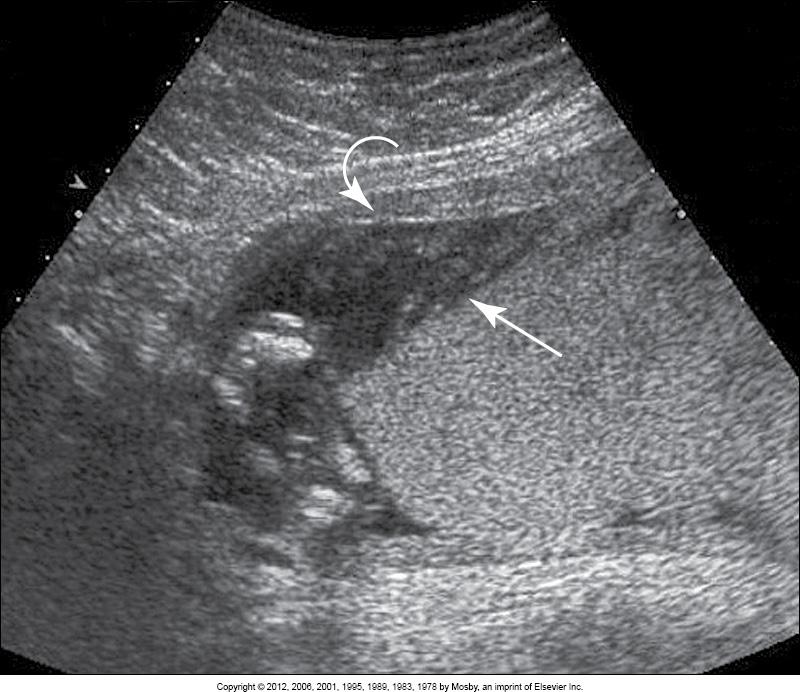

transabdominal image of __

placenta previa